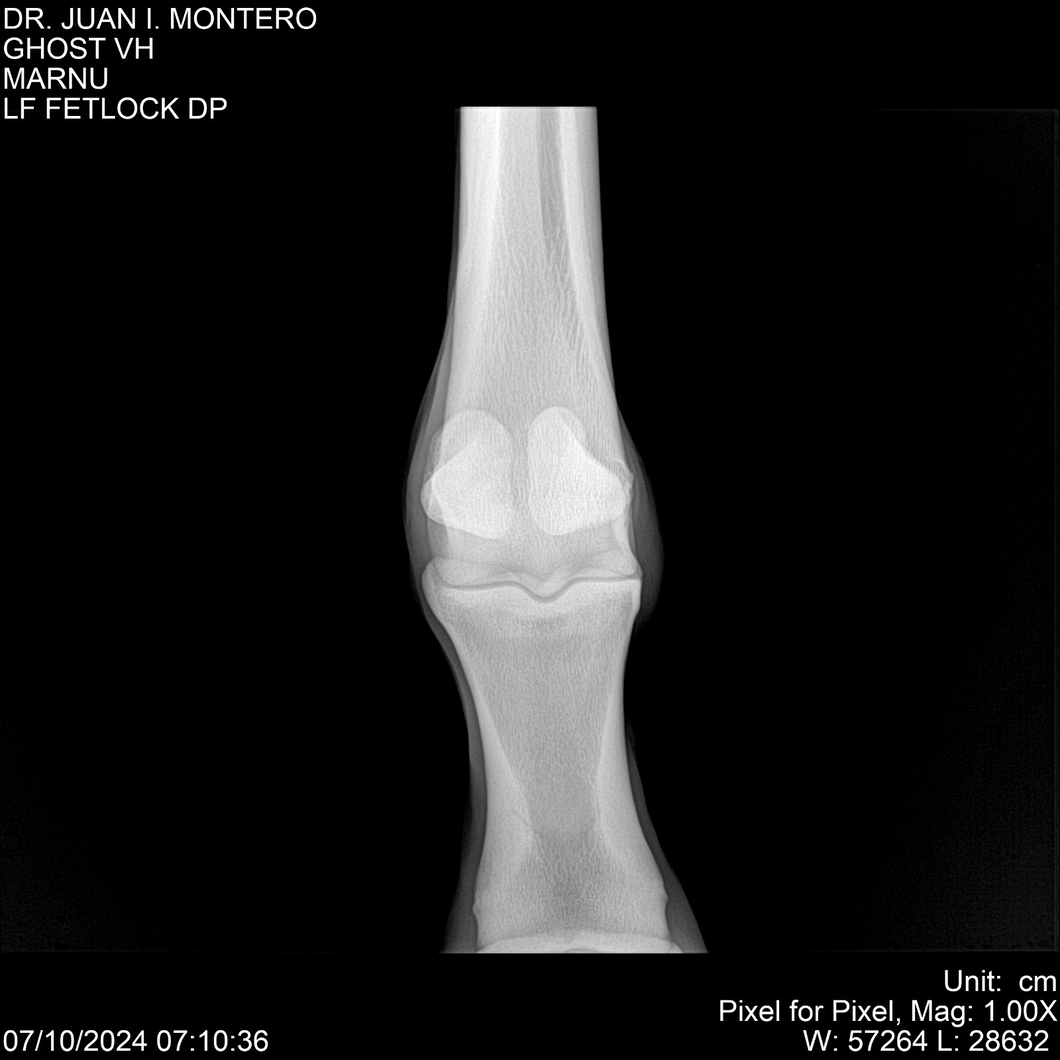

LOTE 15, GHOST VH 🔥 🔥 🔥 Lote Anterior Volver al remate Lote Siguiente Ficha Contacto Montevideo - Ficha del Lote Identificador: #282525 Categoría: Yeguarizos Montevideo - 69 Visualizaciones ClicData Contacto Empresa: Abelenda N. R., Walter Hugo Nombre*: Teléfono* : E-mail* : Mensaje Enviar Registrese gratis Este contenido Exclusivo está disponible sólo para usuarios registrados Ingresar